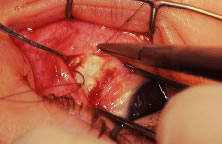

Incision is made into the conjunctiva at the limbus (Fig. 64).

|